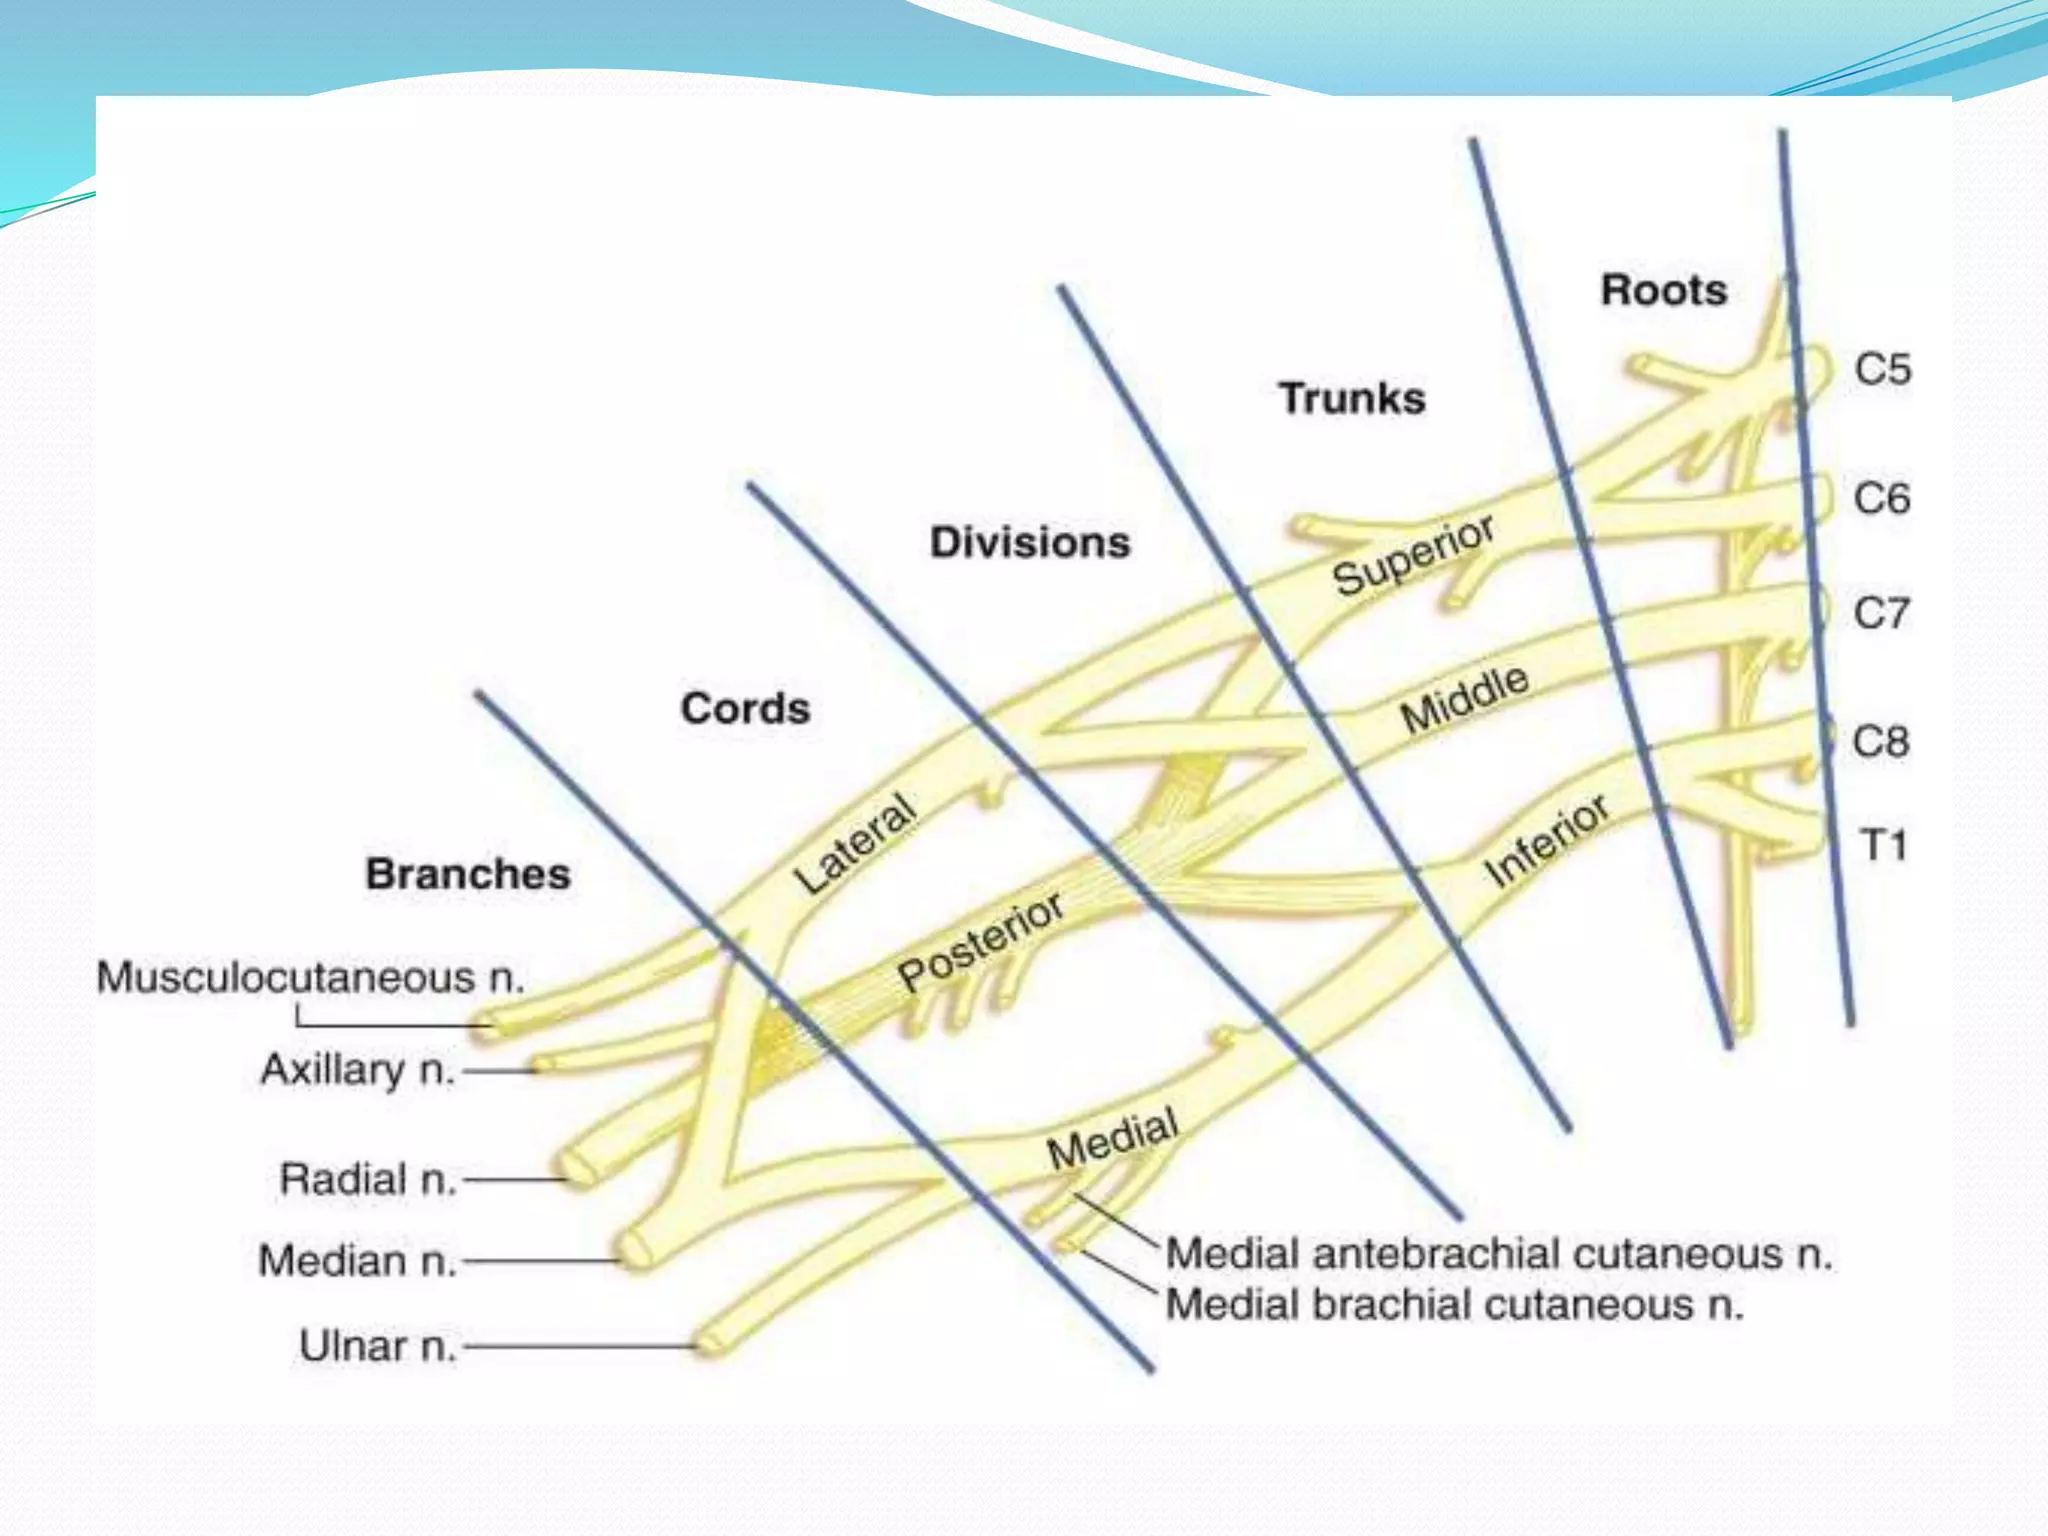

This document provides an overview of brachial plexus anatomy and techniques for brachial plexus nerve blocks. It begins with a description of the brachial plexus formation from cervical and thoracic nerve roots and its branching pattern. Four main approaches for brachial plexus nerve blocks are described: interscalene, supraclavicular, infraclavicular, and axillary. Details are provided on the anatomy and techniques for performing interscalene and supraclavicular brachial plexus blocks. Ultrasound guidance is discussed as an advancement which allows real-time visualization of needle and nerve. Complications are also summarized.